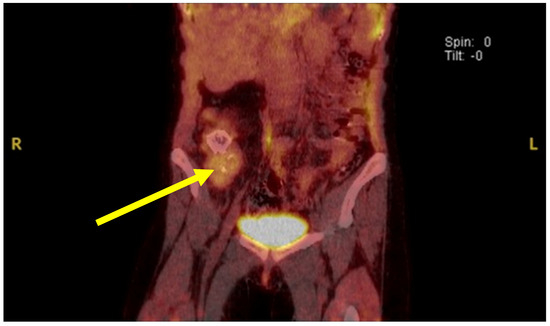

Background: Castleman’s disease (CD), also known as angiofollicular lymph node hyperplasia, describes a rare group of diseases manifesting with enlarged lymph nodes and various inflammatory symptoms. The association between Castleman’s disease, paraneoplastic pemphigus and bronchiolitis obliterans has been described in the literature and

Background: Castleman’s disease (CD), also known as angiofollicular lymph node hyperplasia, describes a rare group of diseases manifesting with enlarged lymph nodes and various inflammatory symptoms. The association between Castleman’s disease, paraneoplastic pemphigus and bronchiolitis obliterans has been described in the literature and is depicted thoroughly in this case. Case Presentation: We present a case of severe bronchiolitis obliterans developing in a 17-year-old female with paraneoplastic pemphigus and unicentric Castleman’s disease. Conclusion: Surgical resection of unicentric Castleman’s disease remains the treatment of choice due to its efficacy in preventing the recurrence of associated morbidity caused by bronchiolitis obliterans and paraneoplastic pemphigus.

Figure 1